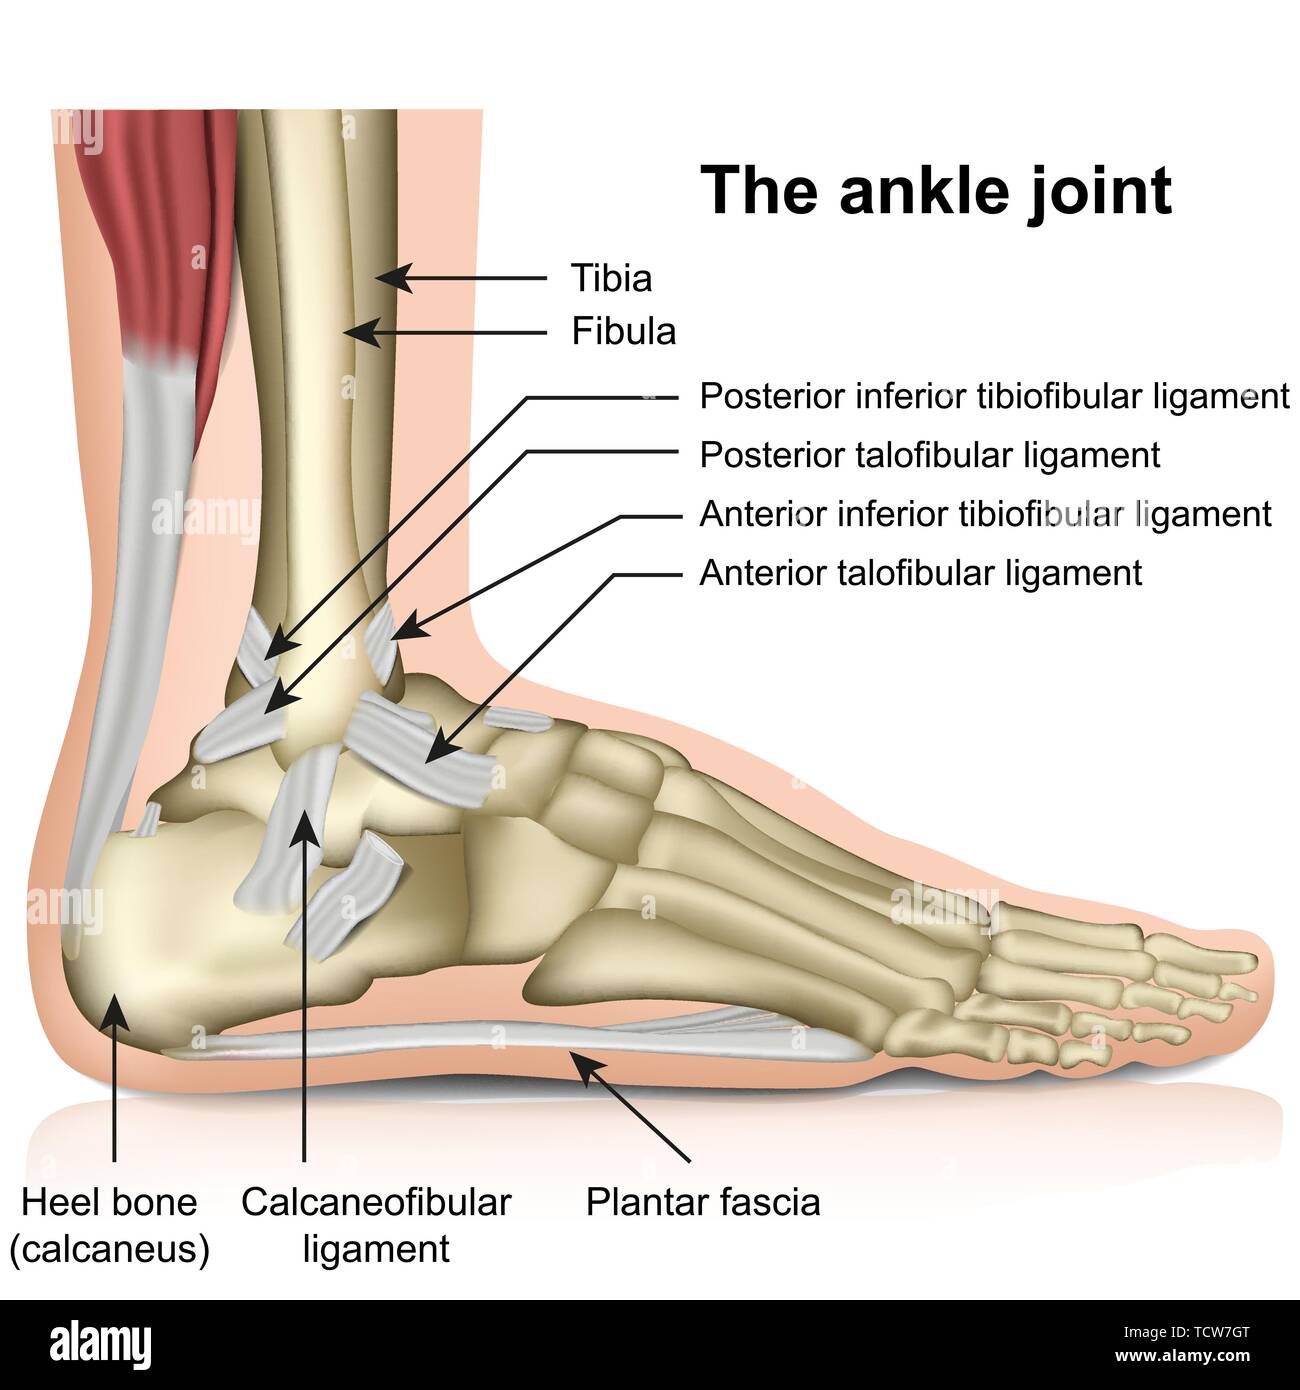

RFTCW7GT–L'articulation de la cheville, les tendons de la cheville anatomie pied eps vector illustration infographie 10

RFTCW7F1–Os du pied et de la cheville d'illustration vectorielle médical isolé sur fond blanc eps 10 Infographie

RF2R3WKY1–Illustration médicale des principales parties des os du pied en vue latérale, avec annotations.

RF2X200ED–L'anatomie de l'articulation de la cheville. Région talocrurale ou os sauteur. Partie du corps humain où le pied et la jambe se rencontrent. Fascia plantaire et tendon d'Achille